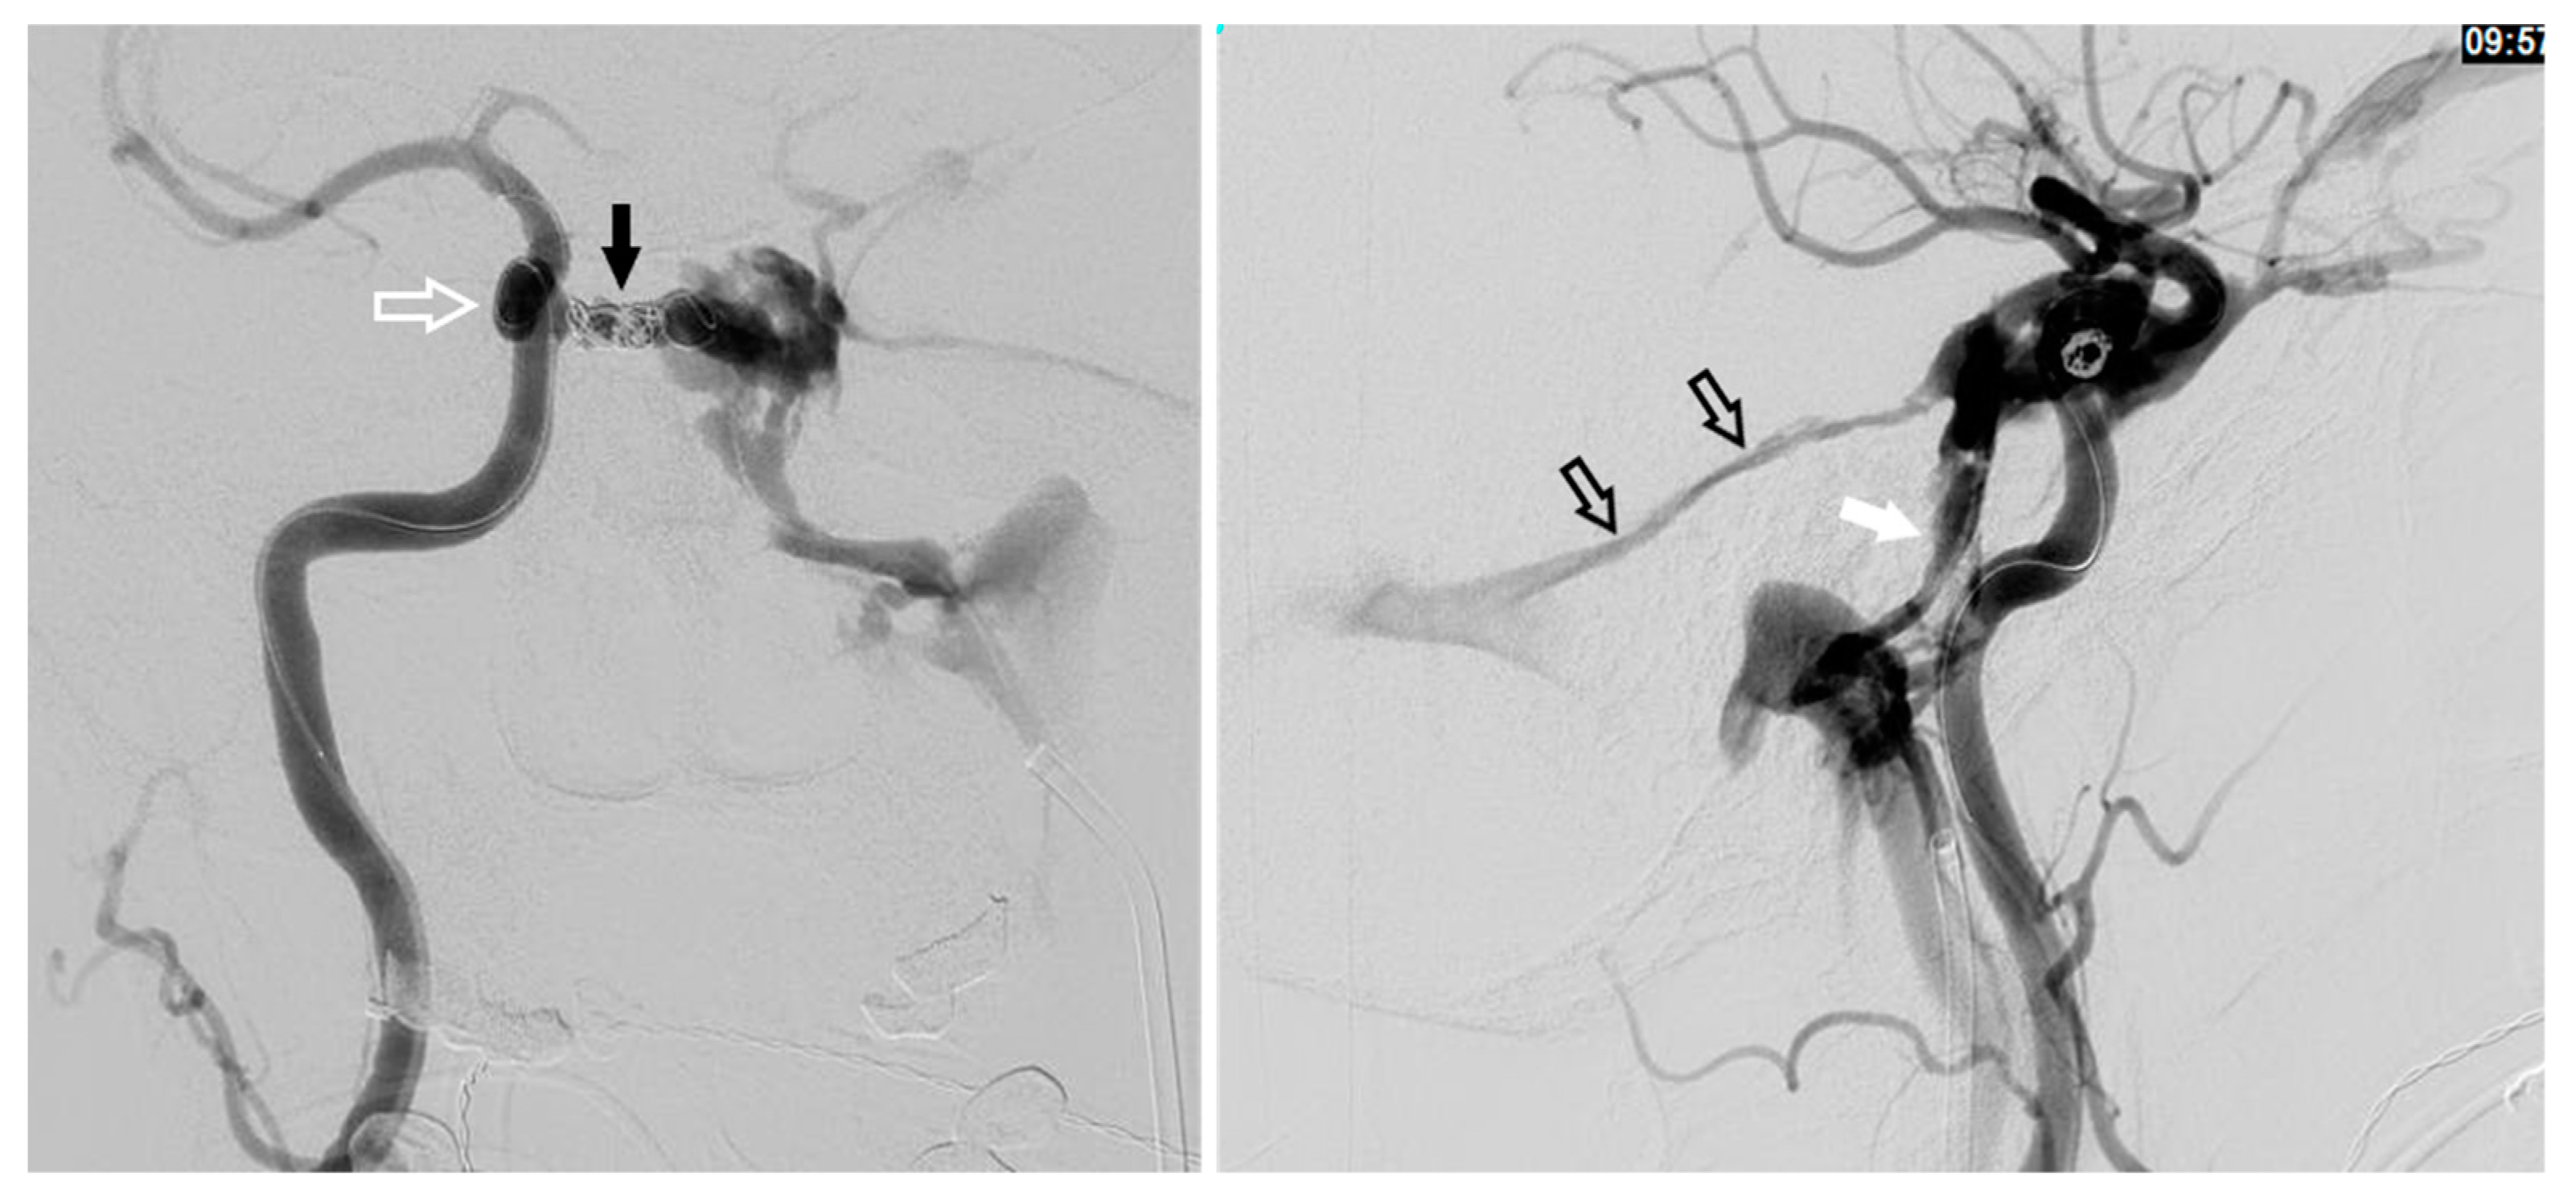

12. Transarterial Via the Cavernous Segment of the ICA (Direct CCF) or Via ICA/ECA Meningeal Branches (Dural CCF)

Figure 10. Demonstrates a right sided direct carotid cavernous fistulas (CCF). An occlusion balloon is placed within the right cavernous internal carotid artery (ICA) (white arrow) across the fistula site. Coils are placed within the intercavernous sinus (black solid arrow) through a transvenous inferior petrosal sinus (IPS) approach (white solid arrow). Note the superior petrosal sinus (black arrows), in the lateral projection, with its acute angle off the transverse sinus.